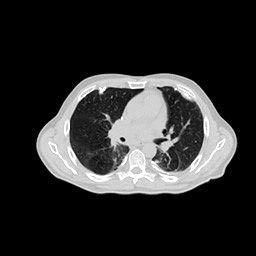

(a) Ground Truth

43.87dB

(b) ASD-POCS

47.96dB

(c) RBP-DIP

34.46dB

(d) DIP

26.63dB

(e) MED50

29.03dB

(f) RED-CNN

16.31dB

Conventional IR methods, even those with the help of regularizations such as total variation, are prone to artifacts when constrained by few-view and limited-angle conditions. However, as illustrated in the first and second rows of Fig.7b, and Fig.8b, these images still contain meaningful information which can be used to guide DIP related reconstruction methods, despite the presence of artifacts.

DIP related methods, which leverage the hierarchical structure of neural networks as a powerful prior, can better handle the aforementioned challenge. However, the original DIP method has its own limitations. It cannot generate detailed images or effectively enhance its accuracy as the number of measurements increases. For instance, in Fig.5a, the ASD-POCS algorithm achieves an approximate SNR gain of dB when the number of views increases from to , while the DIP method only attains an approximate dB gain. This problem is also shown in the last row of Fig.7, and Fig.8. Moreover, the DIP method may produce neural network specific artifacts, as shown in Fig.7d, and Fig.8d. These artifacts are particularly problematic as they are often considered more undesirable than streak artifacts. Radiologists, with their professional experience, can interpret and account for streak artifacts, whereas network specific artifacts may prove more challenging to identify and address.

The proposed RBP-DIP framework combines the two approaches utilizing the newly devised RBP connection so that inherits the benefits of both methods. In Fig.4, the RBP-DIP method’s attainment of a 5dB SNR enhancement over the ASD-POCS method, despite exhibiting a larger loss, underscores the potency of the DIP. Subsequently, the improvement surpassing the original DIP method indicates the efficacy of the RBP connection. Moreover, by employing the RBP connection, neural network specific artifacts can be rectified effectively. As a result, substantial advancements can be shown in Fig.5, Fig.6, Fig.7, and Fig.8.